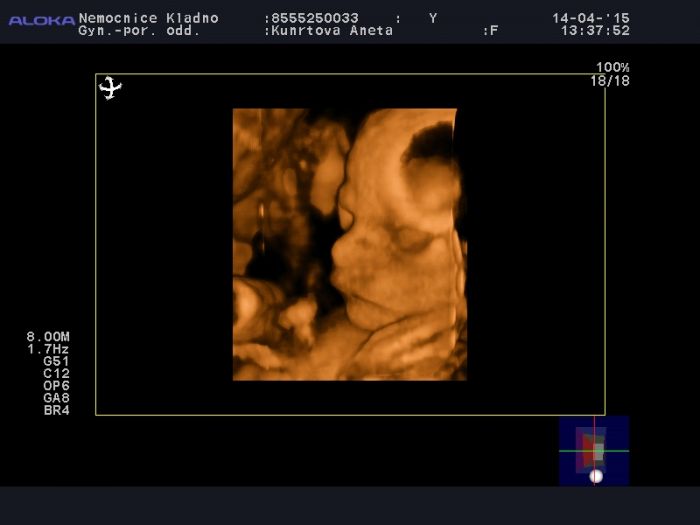

Ahojky holky, tak posílám fotečku Páti. Je hlavičkou nahoru, zdraví jako řípa. Tahal se za pindíka, nohy i ruce dával před obličej, cucal si palec na noze i ruce a nechtěl spolupracovat. Je to prďola. Snad vám to trochu zvedne náladu. Venku je krásně, svítí sluníčko, mám první spáleniny na obličeji a dekoltu, ale nic strašnýho. Už to hnědne :) Ell, snad to bude vše dobré, jak s dcerou, tak s tvojí nožičkou. Pořád vás všechny sleduju a myslím na vás. Držím palečky, ať jsou tam už konečně v bříškách miminka.

Moc krásná fotečka Anet. Je moc dobře, že je vše v pořádku a malej je zdravej..A přetočí se ještě?